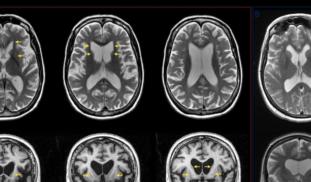

Nodding Disease Syndrome (NDS) is a brain disease that affects children in Uganda. We currently don’t know of the exact cause of NDS, nor have a reliable form of diagnosis. This project aims to answer both of these questions by first investigating a link between a suspected brain protein which might be related to NDS, and a protein related to a parasitic worm disease, and to measure levels of this protein in affected/unaffected children.